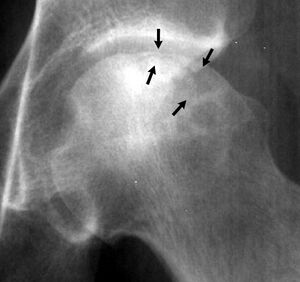

- Chụp X quang phim phẳng thường thu được ở hai mặt phẳng, sử dụng cả phim thẳng và nghiêng (chân chếch). X quang có thể thấy hình ảnh tăng thấu quang dưới màng cứng, đó là “dấu hiệu lưỡi liềm” bệnh lý, cho thấy sự đổ sụp của lớp xương dưới màng cứng.

| III | Xẹp dưới sụn (dấu hiệu lưỡi liềm) mà không làm dẹt chỏm xương đùi |